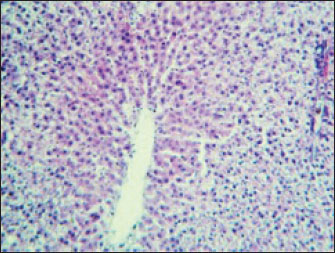

The histopathological results in the TCE group showed that the treatment with TCE for 90 days ( 110 LD50daily) resulted in the infiltration of inflammatory cells, mainly lymphocytes, in portal area with mild fibrosis, hyperplasia of the bile duct (Fig. 3) showed congested central vein, proliferation of Kupffer cells, apoptotic cells and, with dilated sinusoids, while the (Fig. 4) showed severe fatty changes of hepatocytes in the form of cytoplasmic lipid droplets (microvascular steatosis) with proliferation of Kupffer cells. (Fig. 5) showed degenerative changes with necrosis of hepatocytes with proliferation also (Fig. 6). Histopathological section of the liver (group + with oil) showing mild degenerative changes of hepatocytes. In Fig. 7, the histopathological section of the liver (c +group/90 days) showing mild degenerative changes of hepatocytes with few inflammatory cells infiltration (Fig. 8). Finally, in Fig. 9, histological section of the liver (control group) with normal structure.

Fig. 3. Histopathological section of the liver (TCE group/90 days) showing infiltration of inflammatory cells, mainly lymphocytes, in the portal area with mild fibrosis and hyperplasia of the bile duct (H&E stain 100X).

Fig. 4. Histopathological section of the liver (TCE group, 90 days) showing congested central vein, proliferation of Kupffer cells, apoptotic cells and dilated sinusoids (H&E stain 400X).